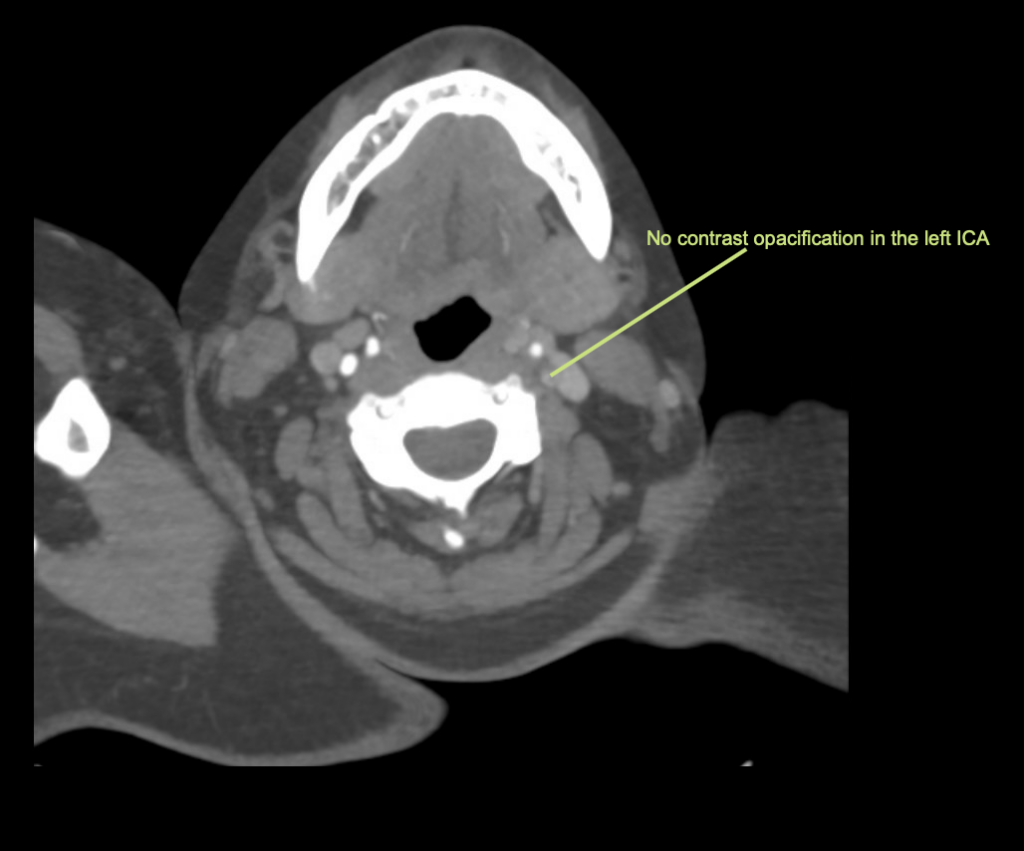

Vengono eseguiti una TAC cerebrale, un angiogramma e una scansione della perfusione cerebrale.

Interpretazione della TAC